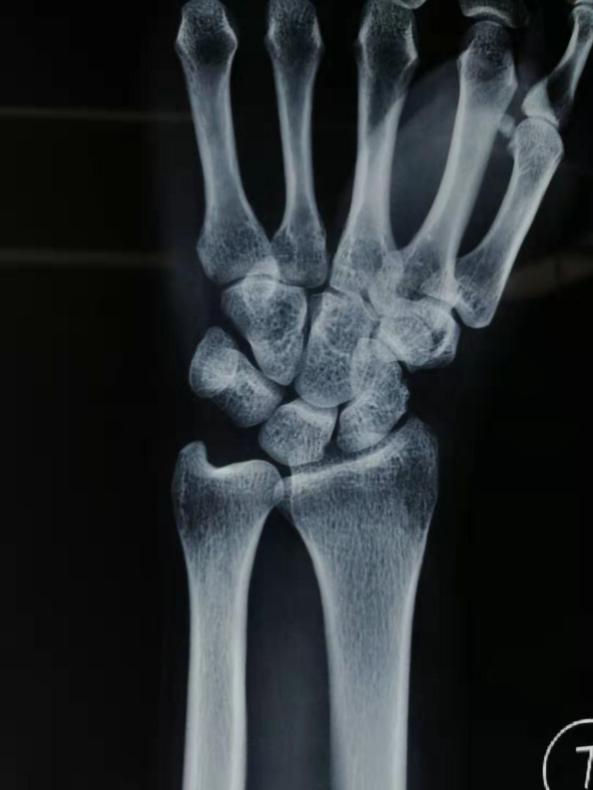

空心釘植入,骨折得到很好的復位加壓

四川友誼醫(yī)院骨科最近成功開展了一例“微創(chuàng)舟骨骨折空心釘固定手術(shù)”。患者曹某某,女,52歲。因“外傷致左腕關(guān)節(jié)疼痛、活動受限1小時”入院。輔助檢查:左腕關(guān)節(jié)CT平掃:左腕舟骨骨折。226日行“左腕舟骨骨折切開復位內(nèi)固定術(shù)”。術(shù)后復查骨折復位良好,內(nèi)固定穩(wěn)定可靠。左腕關(guān)節(jié)活動良好。